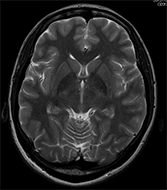

最高の磁場強度である3T(テスラ)MRI装置に更新しました。

当院のMRI装置は、普及している1.5T装置の2倍の磁場強度を有します。約2倍の信号強度が得られるので、より解像度の高い画像を撮影でき、また撮影時間も短縮できるという利点があります。

頭部領域で威力を発揮するのはもちろんのこと、従来の3TMRIの弱点であった腹部や骨盤部でも画像ムラのない高画質な画像が得られます。また、造影剤を使わずに血管を描出したり、心臓の機能を調べたり、さまざまな検査を行うことが可能です。

頭部画像